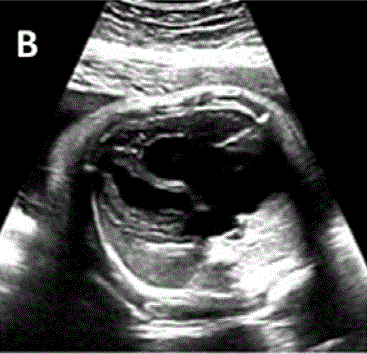

图29胎儿Ebstein异常和TV发育不良。(A)在该胎儿中,严重的三尖瓣反流与进行性心脏增大有关,尤其是右心房(RA)扩张,如这些在19周和34周时的系列图像所示,并且可能与心力衰竭/水肿的演变有关。(B-D)四腔切面中胎儿严重Ebstein异常显示严重心脏扩大的图像。(C)从矢状切面可见广泛的三尖瓣反流(箭头),由于室间隔瓣叶移位,反流起源于TV瓣环下方,甚至向 RV 流出道射流。彩色多普勒和 CW 多普勒显示也有连续的肺动脉反流。(D) 后一项发现表明,右心室无法产生足够的压力来打开肺动脉瓣